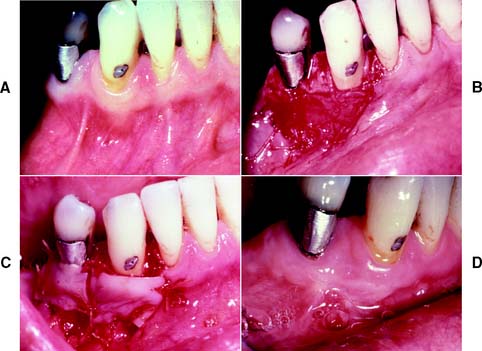

Fig. 6-19 Reconstruction of the interdental papilla. A, Poorly contoured and bulky crowns on maxillary central incisors with loss of interdental papilla. B, Replaced crowns 1 year after cementation with improved tissue contours. However, interdental papilla remains in an apical position. C, Papillary incisions. D, Incisions to harvest retromolar connective tissue combined with incisions to the thin palatal flap. E, Connective tissue harvested in bulk. F, Connective tissue graft trimmed for placement into the papillary area. G, Connective tissue graft placed under buccal and palatal flaps in the interdental area. H, Flaps are sutured over connective tissue graft. I, Three-day postoperative view of papillary graft. J, Final tissue contours around replacement crowns.

(From Azzi R, et al: Surgical reconstruction of the interdental papilla. Int J Periodontics Restorative Dent 18:467, 1998.)